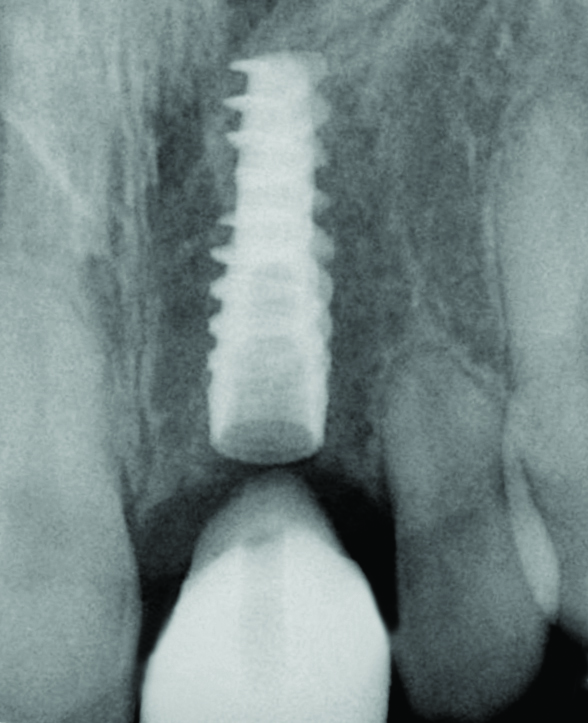

Fig 28. Radiograph on the day of surgery: Implant placement and provisional restoration. Note that the implants are subosseous, as their position is defined by the desired facial free gingival margin position.

Figure 28

Fig 29. One-year radiograph of the definitive restorations on the implants Nos. 8 and 9. Note the crestal bone stability compared to the radiograph taken on the day of surgery in Figure 28.

Figure 29

In the final case, adjacent implants were placed in healed sites No. 8 and No. 9 and provisionalized at the time of surgery (Figure 27 and Figure 28). This case illustrates the effect of platform switching on bone and gingival tissue stability, as well as recognizing that appropriate diameter and spacing is important to maintain ideal ridge contour. The gingival tissue anatomy between implants is characteristically shorter than papilla form between adjacent teeth, and, as a consequence, it is important to incorporate implant designs and procedures that minimize bone-level changes and associated soft-tissue recession. The depth of implant placement was subcrestal relative to the ridge crest, based on the future desired free gingival tissue level, while allowing prosthetic running room. The studies of Barros et al and Veis et al noted that implants positioned subcrestally (as seen in Figure 29) showed better crestal bone preservation than those placed equicrestally or supracrestally.28,29 The implant design used in this case achieves excellent primary stability. Along with the optimal 3-dimensional positioning of the implants and, specifically, the subcrestal placement, as well as the immediate provisionalization protocol, these concepts and implants have contributed to a pleasing esthetic outcome, as seen in Figure 30.